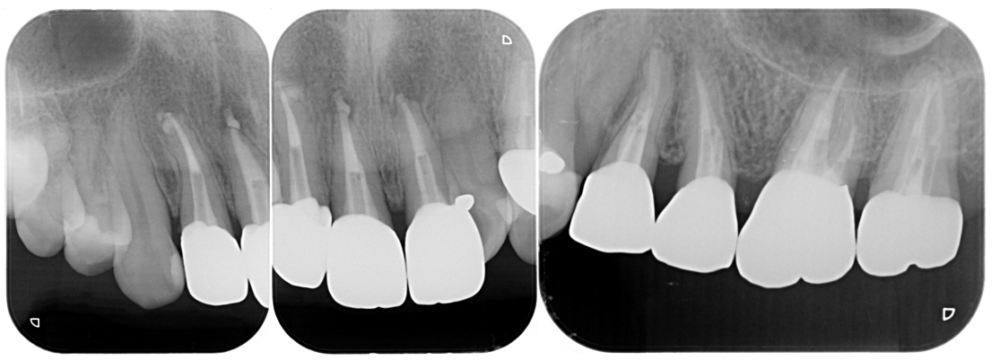

症例5

BEFORE |

AFTER |

| 患者様データ | 60代 女性 |

| 来院時の主訴 | 「鼻炎が治らないので耳鼻科に行ったら歯を治した方が良いと言われた。」 |

| 医院の診断 | 虫歯の再発、歯性上顎洞炎を併発した慢性根尖性歯周炎 |

奥歯の虫歯が原因で蓄膿症になることがあります。患者様は昔から鼻炎があり耳鼻科通いでしたが、歯の治療により鼻炎が治りました。 |